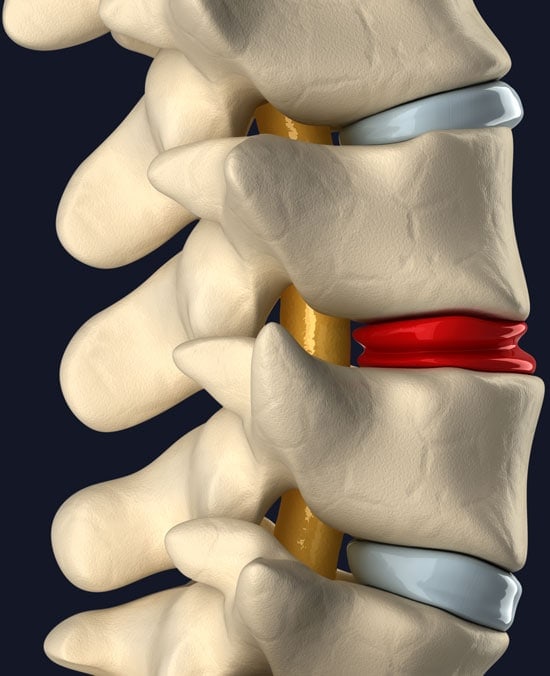

Degenerated disc patients tend to lose disc height which can lead to a wide range of complications.

- Compressed nerves (stenosis)

- Facet joint overload leading to arthritis

- Lax ligaments that result in overall spinal instability

Our advanced Interventional Orthobiologic treatment protocol focuses on Platelet and/or Bone Marrow Concentrate from the patient’s own body deployed to treat disc movement due to lax ligaments and arthritic facet joints.

Advanced Treatments for Torn & Painful Discs

Disc tears are also called annular tears or HIZs (High-Intensity Zones) on MRI images. A patient with a painful and torn disc has “discogenic pain”. The outer covering of the disc can be torn due to injury and painful nerves can grow into the area, leading to low back pain, usually with sitting or activity. In addition, the tear in the disc may lead to noxious chemicals escaping and irritating the spinal nerve, which can lead to sciatica.

Patients with this type of disc damage and pain may benefit from a Regenexx Bone Marrow Concentrate injection procedure.

This highly specialized precise image-guided non-surgical procedure uses cells isolated from the patient’s own bone marrow. The bone marrow is collected using a special needle and advanced imaging guidance during an in-office procedure with your Regenexx Physician. The harvesting procedure is well tolerated by patients and many patients report experiencing no pain. After collection, the Bone Marrow is centrifuged to concentrate the healing cells, and unneeded cells are removed. These cells, along with a preparation of concentrated blood platelets, are injected the same day into the damaged disc, using precise advanced imaging guidance.